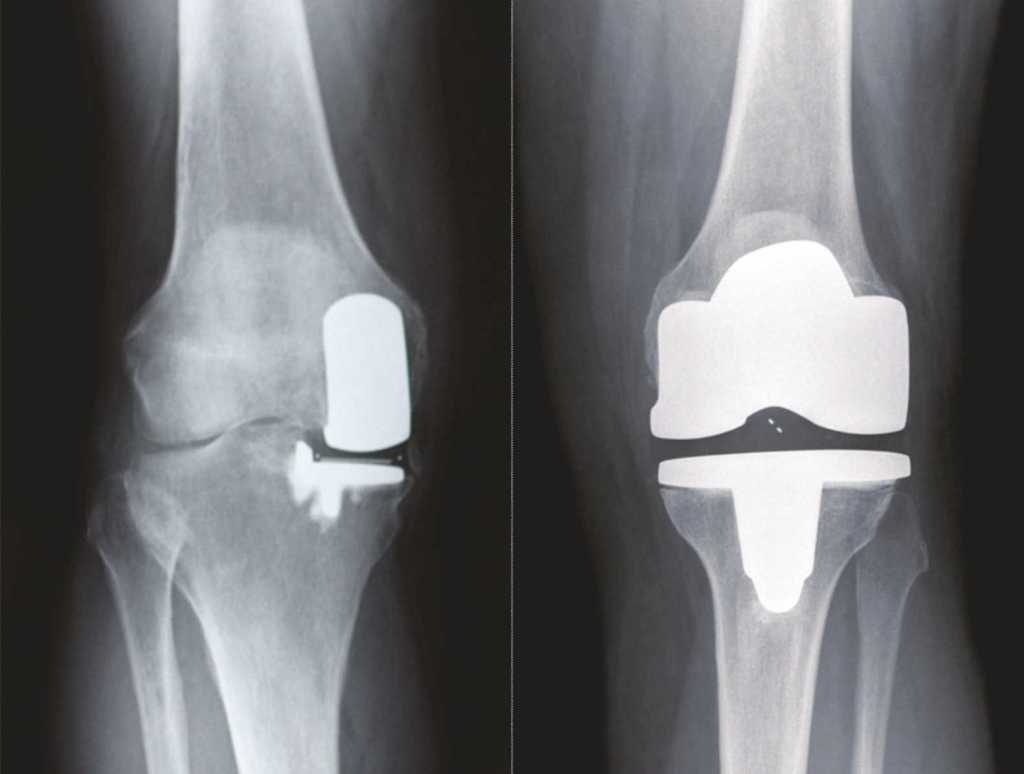

Amerika Birleşik Devletleri’nde her yıl 700.000’den fazla diz protezi yapılmaktadır. Ülkemizde bu sayı 100.000’den fazladır. Total diz protezi en yaygın seçenektir, ancak bazı hastalarda kısmi diz protezi yapılır. Diz sorunlarınızı ve tedavi seçeneklerinizi değerlendirmeden önce, dizinizin nasıl bir eklem olduğunu anlamanızda fayda vardır. İnsan dizi, üç ana bölümden oluşur. Dizin iç kısmı medial bölüm olarak bilinir. Dizin dış bölmesine lateral bölüm denir. Diz kapağı ve uyluk(femur) kemiği arasında bulunan kısıma patellofemoral eklem denir. Diz ekleminin düzgün çalışabilmesi için tendonlar, kıkırdak ve bağlar bu üç kısımda birlikte çalışır. Dizin sadece bir kısmı hasarlı ise diğer kısımlarına dokunmadan tek bir bölümüne protez yapmak mümkündür.

Kısmi Diz Protezi Total Diz Protezi